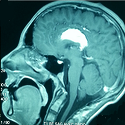

Encéphalopathie de Wernicke compliquant l’hyperémèse gravidique et associée à une myélinolyse centropontique

Hanane Baouahi, Mouhssine Doumiri

PAMJ. 2014; 19: 340. Published 01 December 2014